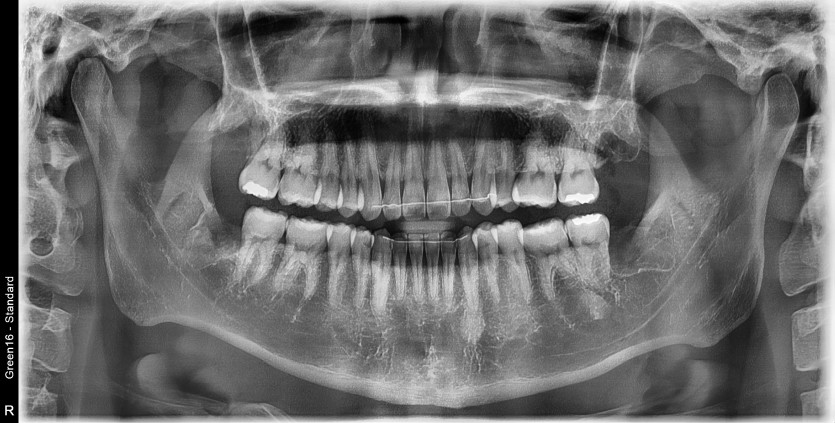

#18,28,38,48 사랑니 발치

구강외과 전문의가 당일 발치했습니다.